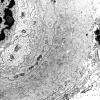

PERIPHERAL NEUROPATHY

11 VASCULITIS - VASCULOPATHY

2 Vasculopathy (3)